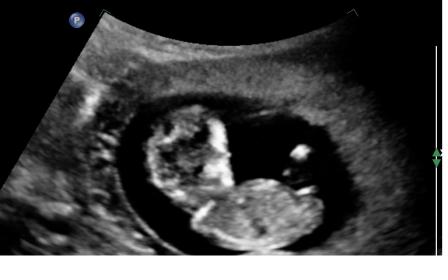

thank you for your guesses, here is another pic where the nub looks different again ( if it is even a nub here)

I'm thinking pink!

I thought girl but good luck and hope you get what you would like

Thinking girl